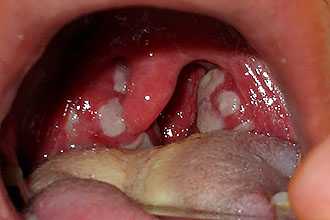

ΠΠ°Π²Π°ΠΉΡΠ΅ ΠΏΠΎΡΠΌΠΎΡΡΠΈΠΌ, ΠΊΠ°ΠΊ Π²ΡΠ³Π»ΡΠ΄ΠΈΡ Π³Π½ΠΎΠΉΠ½Π°Ρ Π°Π½Π³ΠΈΠ½Π° Ρ Π²Π·ΡΠΎΡΠ»ΠΎΠ³ΠΎ Π½Π° ΡΠΎΡΠΎ: ΡΠ»ΠΈΠ·ΠΈΡΡΠ°Ρ ΡΡΠΊΠΎ-ΠΊΡΠ°ΡΠ½Π°Ρ, ΡΠΈΠ»ΡΠ½ΠΎ ΠΎΡΠ΅ΡΠ½Π°Ρ, Π½Π° ΠΌΠΈΠ½Π΄Π°Π»ΠΈΠ½Π°Ρ ΠΎΡΡΡΠΎΠ²ΠΊΠΈ ΠΆΠ΅Π»ΡΠΎ-Π±Π΅Π»ΠΎΠ³ΠΎ Π³Π½ΠΎΡ ΠΈΠ»ΠΈ ΠΆΠ΅ Π²ΡΠ΅ Π»Π°ΠΊΡΠ½Ρ ΠΏΠΎΠΊΡΡΡΡ Π½Π°Π»Π΅ΡΠΎΠΌ.

- ΠΡΠΈ Π³Π½ΠΎΠΉΠ½ΠΎΠΉ Π»Π°ΠΊΡΠ½Π°ΡΠ½ΠΎΠΉ Π°Π½Π³ΠΈΠ½Π΅ ΠΏΠΎΡΠ°ΠΆΠ΅Π½ΠΈΠ΅ ΠΌΠΈΠ½Π΄Π°Π»ΠΈΠ½ ΠΏΡΠΎΠΈΡΡ ΠΎΠ΄ΠΈΡ Π² ΠΎΠ±Π»Π°ΡΡΠΈ Π»Π°ΠΊΡΠ½, ΠΏΡΠΎΡΠ΅ΡΡ Π½Π΅ ΡΠ°ΡΠΏΡΠΎΡΡΡΠ°Π½ΡΠ΅ΡΡΡ Π·Π° ΠΏΡΠ΅Π΄Π΅Π»Ρ ΠΌΠΈΠ½Π΄Π°Π»ΠΈΠ½. ΠΡΠΈ ΠΎΡΠΌΠΎΡΡΠ΅ Π²ΡΡΠ²Π»ΡΠ΅ΡΡΡ Π²ΡΡΠ°ΠΆΠ΅Π½Π½Π°Ρ Π³ΠΈΠΏΠ΅ΡΠ΅ΠΌΠΈΡ ΠΈ ΠΎΡΠ΅ΠΊ Π½Π΅Π±Π½ΡΡ ΠΌΠΈΠ½Π΄Π°Π»ΠΈΠ½, Π° ΡΠ°ΠΊΠΆΠ΅ ΡΠ°ΡΡΠΈΡΠ΅Π½ΠΈΠ΅ Π»Π°ΠΊΡΠ½. ΠΠ° ΠΌΠΈΠ½Π΄Π°Π»ΠΈΠ½Π°Ρ ΠΎΠ±ΡΠ°Π·ΡΠ΅ΡΡΡ ΡΠΈΠ±ΡΠΎΠ·Π½ΠΎ-Π³Π½ΠΎΠΉΠ½ΡΠΉ Π½Π°Π»Π΅Ρ ΠΆΠ΅Π»ΡΠΎ-Π±Π΅Π»ΠΎΠ³ΠΎ ΡΠ²Π΅ΡΠ°. ΠΡΠΎΡ Π½Π°Π»Π΅Ρ ΡΠ΄Π°Π»ΡΠ΅ΡΡΡ Π»Π΅Π³ΠΊΠΎ, Π½Π° ΠΌΠ΅ΡΡΠ΅ Β«ΠΏΡΠΎΠ±ΠΎΠΊΒ» Π½Π΅ ΠΎΡΡΠ°Π΅ΡΡΡ ΠΊΡΠΎΠ²ΠΎΡΠΎΡΠ°ΡΠΈΡ ΡΠ»Π΅Π΄ΠΎΠ².

- ΠΠ½ΠΎΠΉΠ½Π°Ρ ΡΠΎΠ»Π»ΠΈΠΊΡΠ»ΡΡΠ½Π°Ρ Π°Π½Π³ΠΈΠ½Π° Ρ Π°ΡΠ°ΠΊΡΠ΅ΡΠΈΠ·ΡΠ΅ΡΡΡ Π³Π»ΡΠ±ΠΎΠΊΠΈΠΌ ΠΏΠΎΡΠ°ΠΆΠ΅Π½ΠΈΠ΅ΠΌ ΡΠΎΠ»Π»ΠΈΠΊΡΠ»ΡΡΠ½ΠΎΠ³ΠΎ Π°ΠΏΠΏΠ°ΡΠ°ΡΠ° (Π»ΠΈΠΌΡΠ°ΡΠΈΡΠ΅ΡΠΊΠΈΡ ΡΠ·Π΅Π»ΠΊΠΎΠ²) ΠΌΠΈΠ½Π΄Π°Π»ΠΈΠ½. ΠΠ½ΠΈ ΠΎΡΠ΅ΡΠ½ΡΠ΅, ΡΡΠΊΠΎ-ΠΊΡΠ°ΡΠ½ΠΎΠ³ΠΎ ΡΠ²Π΅ΡΠ°, Π²ΡΡΡΡΠΏΠ°ΡΡΠΈΠ΅ Π½Π° ΠΏΠΎΠ²Π΅ΡΡ Π½ΠΎΡΡΠΈ ΡΠ»ΠΈΠ·ΠΈΡΡΠΎΠΉ ΠΎΠ±ΠΎΠ»ΠΎΡΠΊΠΈ, Π³Π½ΠΎΠΉΠ½ΡΠ΅ Π½Π°Π»Π΅ΡΡ Π½Π΅Π»ΡΠ·Ρ Π»Π΅Π³ΠΊΠΎ ΡΠ΄Π°Π»ΠΈΡΡ ΡΠΏΠ°ΡΠ΅Π»Π΅ΠΌ. Π‘Π»ΠΈΠ²Π°ΡΡΡ Π΄ΡΡΠ³ Ρ Π΄ΡΡΠ³ΠΎΠΌ, Π³Π½ΠΎΠΉΠ½ΡΠ΅ ΠΎΡΠ°Π³ΠΈ ΠΌΠΎΠ³ΡΡ ΠΎΠ±ΡΠ°Π·ΠΎΠ²ΡΠ²Π°ΡΡ Π°Π±ΡΡΠ΅ΡΡΡ.

ΠΠΎΠ»ΠΎΡΡΡ ΡΡΠ°: ΡΠ»Π΅Π²Π° β Π·Π΄ΠΎΡΠΎΠ²Π°Ρ, ΡΠΏΡΠ°Π²Π° β ΠΏΡΠΈ ΠΎΡΡΡΠΎΠΌ Π±Π°ΠΊΡΠ΅ΡΠΈΠ°Π»ΡΠ½ΠΎΠΌ ΡΠΎΠ½Π·ΠΈΠ»Π»ΠΈΡΠ΅ (Π°Π½Π³ΠΈΠ½Π΅).Π‘ΠΈΠΌΠΏΡΠΎΠΌΡ Π³Π½ΠΎΠΉΠ½ΠΎΠΉ Π°Π½Π³ΠΈΠ½Ρ Ρ Π²Π·ΡΠΎΡΠ»ΡΡ ΠΈ Ρ Π΄Π΅ΡΠ΅ΠΉ ΡΡ ΠΎΠΆΠΈ. ΠΠ±ΡΡΠ½ΠΎ Π±ΠΎΠ»ΡΠ½ΡΠ΅ ΠΏΡΠ΅Π΄ΡΡΠ²Π»ΡΡΡ ΡΠ»Π΅Π΄ΡΡΡΠΈΠ΅ ΠΆΠ°Π»ΠΎΠ±Ρ:

- Π³ΠΈΠΏΠ΅ΡΠ΅ΠΌΠΈΡ ΠΈ ΠΎΡΠ΅ΡΠ½ΠΎΡΡΡ ΠΌΠΈΠ½Π΄Π°Π»ΠΈΠ½, Π° ΡΠ°ΠΊΠΆΠ΅ Π½Π°Π»ΠΈΡΠΈΠ΅ Π³Π½ΠΎΠΉΠ½ΡΡ Π½Π°Π»Π΅ΡΠΎΠ² Π² Π²ΠΈΠ΄Π΅ Π±Π΅Π»ΠΎ-ΠΆΠ΅Π»ΡΡΡ Β«ΠΏΡΠΎΠ±ΠΎΠΊΒ» Π½Π° Π½ΠΈΡ .